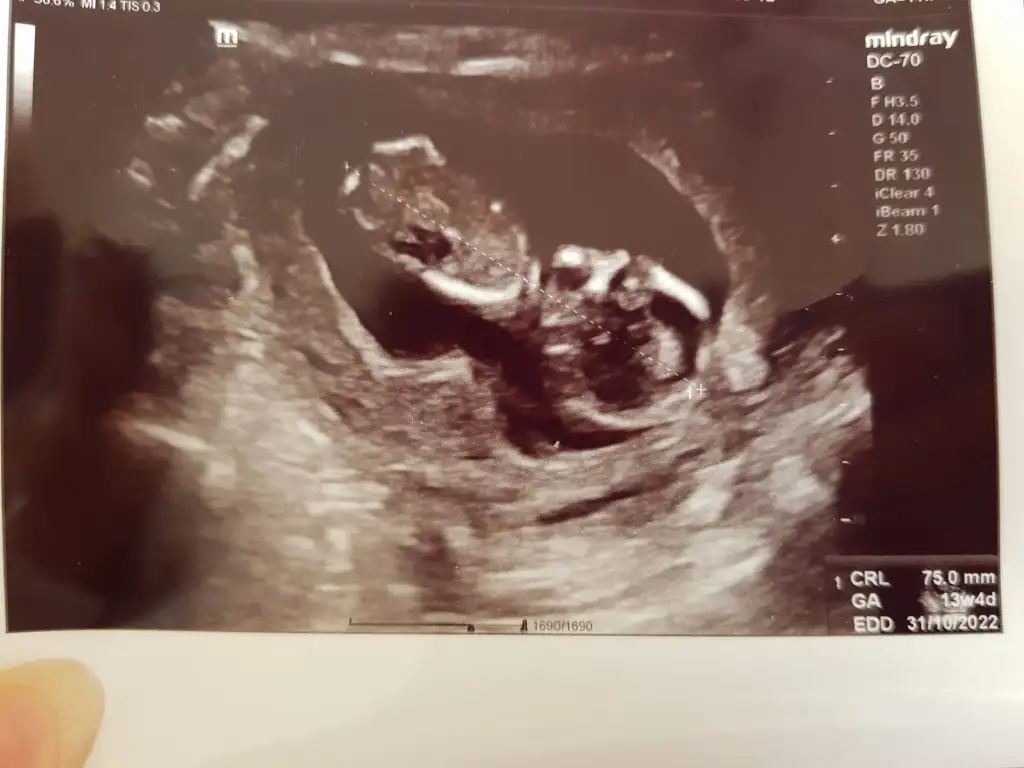

2.Resim 11+5

3.Resim 13+4